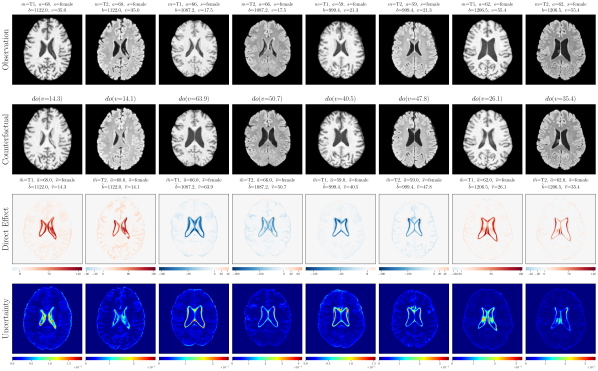

4.2 Brain Imaging Counterfactuals

To demonstrate our model’s ability to produce faithful high-fidelity counterfactuals of real data, we extend our approach to a real-world scenario involving brain MRI scans from the UK Biobank (Sudlow et al., 2015). As before, we start with an assumed causal generative process involving a set of observed variables as shown in Figure 4(a). The causal graph is medically informed and extends the scenario in Pawlowski et al. (2020) by: (i) introducing an additional MRI Sequence (T1/T2) binary variable to enable discrete counterfactuals; (ii) having directly. We used a scaled-up version of our exogenous prior HVAE as ’s mechanism and used (conditional) normalizing flows for the other mechanisms (see Appendix A.1). As shown in Figure 4, our deep SCM is capable of producing qualitatively sharp counterfactuals with localised changes according to the intervened upon parent(s) and the associated causal graph. Importantly, the identity of subjects is well preserved in all cases including null-interventions (i.e. nothing). Table 2 shows the counterfactual effectiveness results from random interventions on each variable. We observed satisfactory initial counterfactual effectiveness and significant improvements of post counterfactual training, demonstrating the merit of the proposed approach. Please refer to Appendix A.2 for notes on abduction uncertainty and D for additional results.

D.3 Extra Results

‘Age’ counterfactuals

Post counterfactual training:

‘Brain Volume’ counterfactuals

‘Ventricle Volume’ counterfactuals